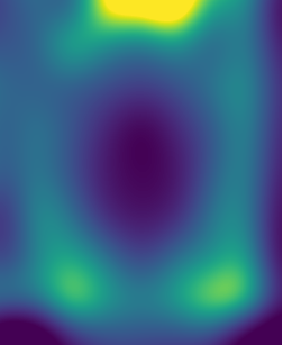

Figure 1: Reconstruction results for R = 3, with (1(a)) the fully sampled image, (b) the zero-filled image, (c) the reconstruction with no bias field estimation, (d) the joint reconstruction with bias field estimation using N4. The first three rows show reconstruction results for an HCP image, its zoomed-in version and the corresponding bias field. The next three rows show results for an in-house measured image. For visualization purposes, MR images are clipped to [0, 1.2] and bias fields, to [0.5, 1.8].

The quantitative improvement is also supported by the visual inspection of the images given in Figure 1. From the HCP image, one can observe that the level of artifacts is reduced with the proposed method. This becomes more evident in the zoomed-in images. The red arrow points to a part of the image where the proposed method can reconstruct the structures faithfully, whereas the baseline method struggles. Aliasing artifacts are globally suppressed better with the joint reconstruction method. Similarly, for the in-house measured image, the grey matter structure that the red arrow points to is not reconstructed in the baseline method, whereas it again appears with the proposed method.